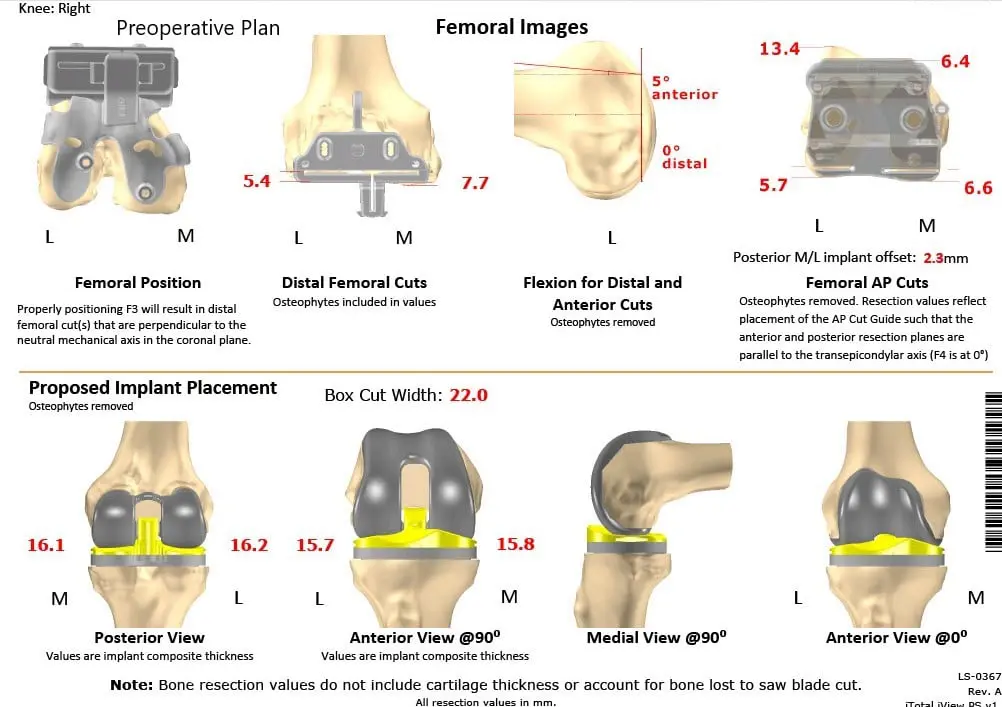

As a part of assessment and planning, a preoperative CAT scan of the lower extremities was obtained a few weeks prior to surgery. Detailed images were acquired for accurate assessment of the patient’s anatomy and biomechanics. Entire data was utilized to construct custom implants and instruments unique for the patient.

Complete Orthopedics patient-specific surgical plan for a customized right total knee replacement in a 73-year-old male with arthritis.